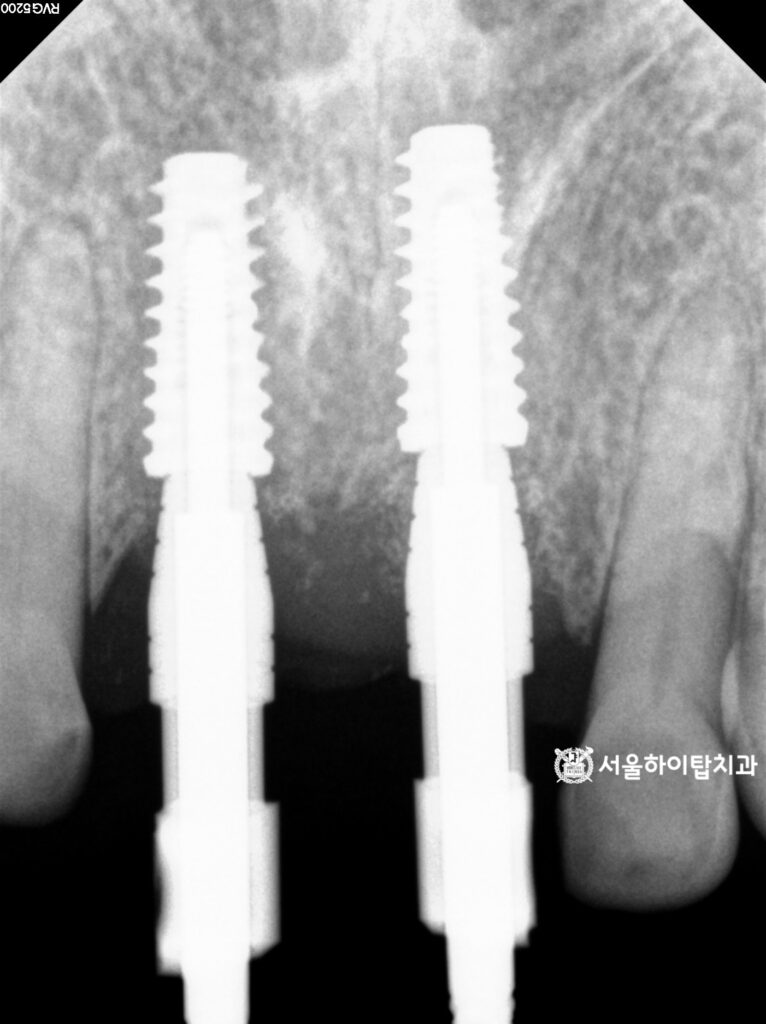

3. 수술 완료

상기 시뮬레이션을 기반으로

예측한 위치에 임플란트가

식립된 것을 확인할 수 있습니다.

특히 위턱의 경우

골 이식이 함께 이루어지면서,

임플란트가 골 내에서 안정적으로

자리 잡은 모습을 관찰할 수 있습니다.

이를 통해 수술 계획대로

심미, 기능 안정성이 확보된

상태임을 확인할 수 있습니다.